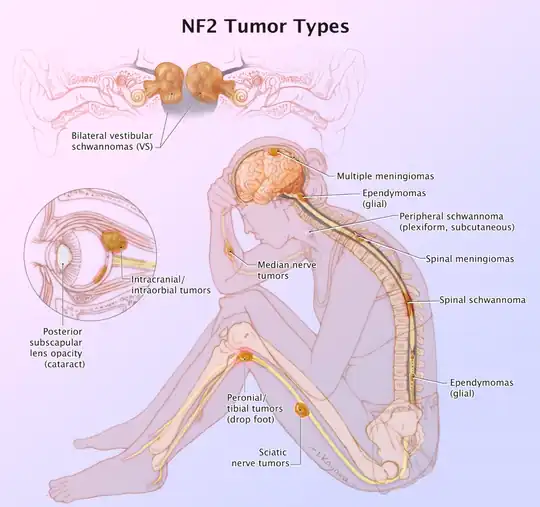

| Other names | multiple inherited schwannomas, meningiomas, and ependymomas (MISME syndrome)) |

| Figure of various morbidities associated with neurofibromatosis type II.[1] | |

Neurofibromatosis type II (also known as MISME syndrome – multiple inherited schwannomas, meningiomas, and ependymomas) is a genetic condition that may be inherited or may arise spontaneously, and causes benign tumors of the brain, spinal cord, and peripheral nerves. The types of tumors frequently associated with NF2 include vestibular schwannomas, meningiomas, and ependymomas. The main manifestation of the condition is the development of bilateral benign brain tumors in the nerve sheath of the cranial nerve VIII, which is the "auditory-vestibular nerve" that transmits sensory information from the inner ear to the brain. Besides, other benign brain and spinal tumors occur. Symptoms depend on the presence, localisation and growth of the tumor(s), in which multiple cranial nerves can be involved.[2] Many people with this condition also experience vision problems. Neurofibromatosis type II (NF2 or NF II) is caused by mutations of the "Merlin" gene,[3] which seems to influence the form and movement of cells. The principal treatments consist of neurosurgical removal of the tumors and surgical treatment of the eye lesions. Historically the underlying disorder has not had any therapy due to the cell function caused by the genetic mutation.